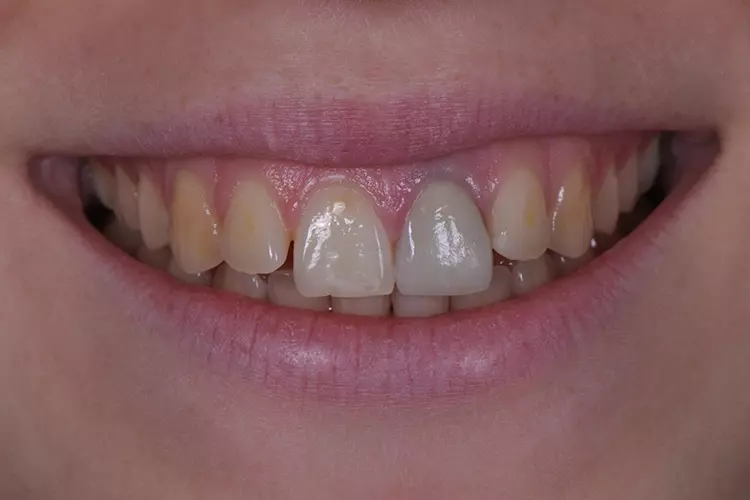

Im Rahmen des Erstgespräches berichtete die junge Patientin von einem Sturzereignis, bei dem der Schneidezahn frakturierte. Ihr damaliger Zahnarzt führte eine Wurzelkanalbehandlung durch und versorgte den Zahn mit einer Krone aus Lithiumdisilikat. Das anfänglich sehr ansprechende ästhetische Behandlungsergebnis hätte sich jedoch nach der Eingliederung mit der Zeit verändert und die Patientin stellte eine zunehmende Verfärbung der Frontzahnkrone fest (Abb. 2 und 3).

Dies kann aus einer nachträglich eingetretenen Verfärbung des devitalen Zahnes resultieren. Durch die sehr hohe Transluzenz der Glasphase einer Lithiumdisilikat-Restauration kann die dunkle Stumpffarbe durchschlagen und zu einem ästhetisch störenden „Grauschleier“ führen. In einem intensiven Beratungs- und Aufklärungsgespräch wurden der Patientin die Schwierigkeiten und Herausforderungen einer Einzelzahnkrone in der ästhetischen Zone bei einer hohen Lachlinie mit Exposition der Gingiva dargestellt.

Manche Details wie die Verfärbung der Gingiva wären nicht korrigierbar und verringerten die Vorhersagbarkeit eines optimalen ästhetischen Resultates. Die Neuversorgung dient der Verbesserung der ästhetischen Situation, eine perfekte Kopie des Zahnes 11 wird nicht zu erzielen sein, da die verfärbte Wurzel bestehen bleibe.

Trotz der aufgeführten Risiken und Unwägbarkeiten wünschte die junge Patientin eine Neuversorgung des Zahnes, um eine bestmögliche Ästhetik zu erreichen. Gleichzeitig sollten ihre natürliche Zahnfarbe und die individuelle Zahnstellung nicht verändert werden.